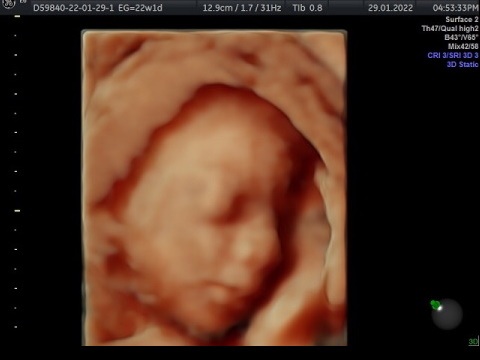

Se realiza entre la semana 18 a 24 de la gestación. Es un estudio que nos ayuda a determinar si tu bebe tiene alguna malformación en su anatomía. El ultrasonido estructural es un estudio realizado por ginecólogos con subespecialidad en Medicina Materno Fetal. Revisamos estructuras internas del cerebro, corazón , riñones , pulmones, manos y pies para ver si no tiene alteraciones en su anatomía. Se realiza además medición de tus arterias uterinas para estimar riesgo de preeclampsia y al final de tu estudio se realiza 3D , 4D. 5D para que conozcas la carita de tu bebe. Tiene una duración de 1 hora y un costo de $1800

El ultrasonido estructural o sonograma genético complementario, es un estudio muy importante que permite detectar o descartar una alta cantidad de defectos en el desarrollo físico del feto.